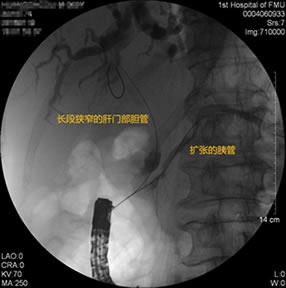

胃毕-Ⅱ术后球囊扩张狭窄胆管 胃毕-Ⅱ术后支架植入 胃毕-Ⅱ术后胆管胰管扩张